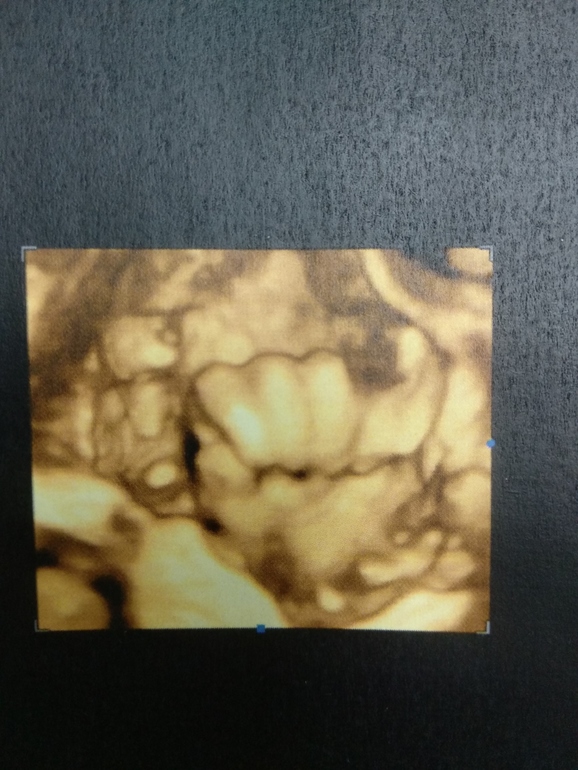

Утром были на последнем скрининге..

Длинна предположительно 46

Вес 2363

Сб 157уд/мин

Плацента 2ст

Так и лежит головой вниз, как я и думала пяткой мне под правое ребро

Плацента на плече

Доплер в пределах нормы:

Мои: 1,12 и 0,83

Его: 0,83 и 0,96

Среднемозговая 2,06

Меня волновали кровотоки (со старшим были нарушения и количество вод), но обошлось.. сказал больше показаний к УЗИ не видит, только ктг.

Лицо не показал, только кулак )) вредина

Сказал родится средним ) чтобы это значило )))